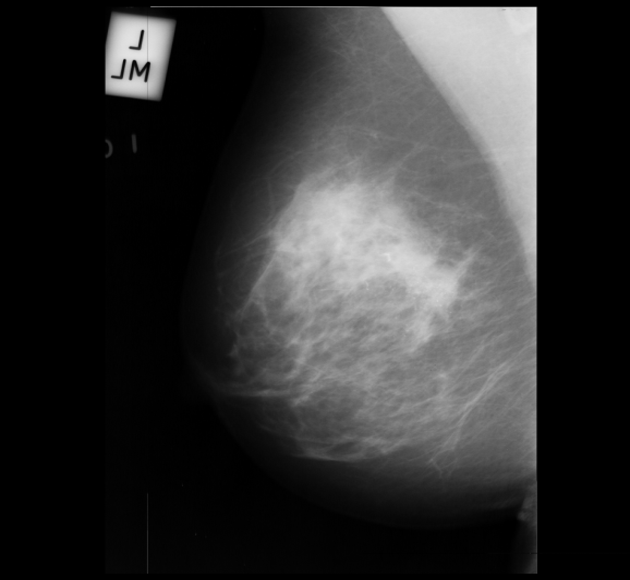

Neural networks require a large number of images as input for the training purposes. Because of limited resources of large dataset availability, the dataset used for this research is mini MIAS dataset [10]. It comprises of total 322 images which are further divided into a number of classes. Original size of each image in the dataset is 10241024. Sample images are shown in Figure 1.

Figure 5 shows a few sample images obtained after segmentation.